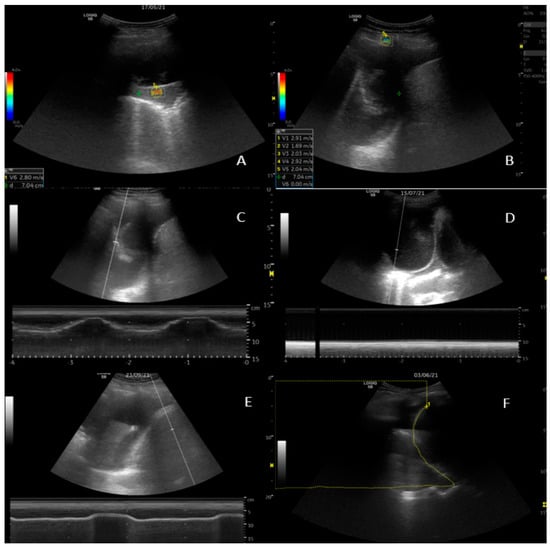

2.4. M-Mode

Diaphragm movement was measured at the area of largest amplitude of the diaphragm with the targeting line. Lung movement (visceral pleura) was assessed at the perpendicular point of thoracentesis, as illustrated in Figure 1. Amplitude results are provided in centimetres with two decimals.

2.5. 2D Shear Wave Elastography (SWE)

Measurements from three structures were made: five recordings of the parietal pleura, the pleural effusion superficially to the lung, and the visceral pleura/consolidation perpendicular to the transducer (Figure 1). Care was taken to apply minimal pressure from the transducer to the chest wall. Readings were obtained while breath was held. A region of interest (ROI) was selected upon the elastogram, providing adequate shear wave propagation, and was adjusted to size. Measurements were obtained in m/s [31].

SWE did not result in superior diagnostic ability of NEL in our study. Obtaining usable ROI was reasonable easy. We observed that there was a high degree of measurement unreliability within the same ROI, as exemplified in Figure 1. Even though care was taken to conform to attaining optimal imaging, the patient population was frail, and, for example, breath holding proved difficult.

Figure 1. Ultrasound examinations. (A) 2D shear wave elastography (SWE) of visceral pleura. (B) SWE of parietal pleura with 5 readings recorded in the lower left corner. (C) M-mode measurement of lung movement. The respiratory pattern is seen in the curves on the bottom of the screen. (D) M-mode measurement of lung movement. Here, absence of lung movement is illustrated by the flat line below the 2-D image. (E) M-mode measurement of diaphragm movement. (F) Area-method measurement of area above the diaphragm during inspiration.